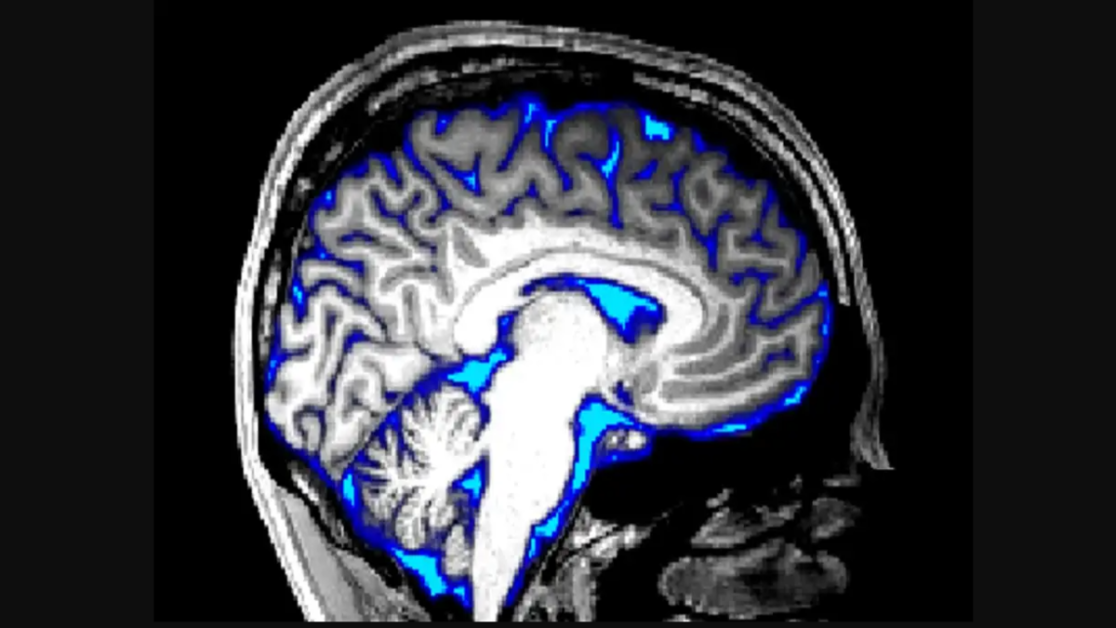

वैज्ञानिकों का कहना है कि अब हैरान कर देने वाली बात ये सामने आई है कि यह जागते हुए इंसानों में भी काम कर सकता है। दिमाग में एक खास तरह के तरल पदार्थ का फ्लो पाया गया है जिसे सेरीब्रोस्पाइनल फ्ल्यूड (cerebrospinal fluid) कहते हैं। 2012 में इससे संबंधित एक खोज की गई थी। जिसमें पाया गया था कि दिमाग के डिस्पोजल सिस्टम के लिए यही फ्ल्यूड काम करता है जो कि दिमाग में भेजा जाता है और महीन ट्यूब्स में से होता हुआ पास होकर बाहर निकल जाता है। इसे ग्लिम्फैटिक सिस्टम (glymphatic system) का नाम दिया गया।

इस बारे में रिसर्च कहती है कि यह फ्ल्यूड कुछ हानिकारक तत्वों को भी दिमाग से बाहर निकाल ले जाता है जो कि अल्जाईमर और पार्किंसन जैसे डिसॉर्डर के लिए कारण माने जाते हैं। इनमें बीटा अमायलॉयड और एल्फा साइन्यूक्लीन आदि का नाम शामिल है। स्टडी से जुड़े मिस्टर ल्यूस की टीम ने इसके लिए अलग-अलग टूलों और स्कैनिंग तकनीकों का इस्तेमाल किया। रिसर्च में 20 वालेंटियर शामिल किए गए जिनके सामने देखने के लिए एक स्क्रीन रखी गई। इन्हें एक ऐसा विजुअल पैटर्न दिखाया गया जिससे कि दिमाग पर भारी जोर पड़े।

पैटर्न को देखने के बाद इन लोगों के रक्त के प्रवाह में तेजी पाई गई। वहीं, स्क्रीन जब काली हो जाती थी तो ब्लड फ्लो फिर से कम हो जाता था और दिमाग में सेरीब्रोस्पाइनल फ्ल्यूड का प्रवाह बढ़ जाता था। वैज्ञानिक अभी इसके बारे में और अधिक रिसर्च कर रहे हैं और इस फ्ल्यूड के काम करने की प्रणाली को समझने की कोशिश कर रहे हैं। जल्द ही यह संभव हो सकता है कि दिमाग में फ्लश आउट सिस्टम को जागने के समय भी एक्टिवेट किया जा सके।